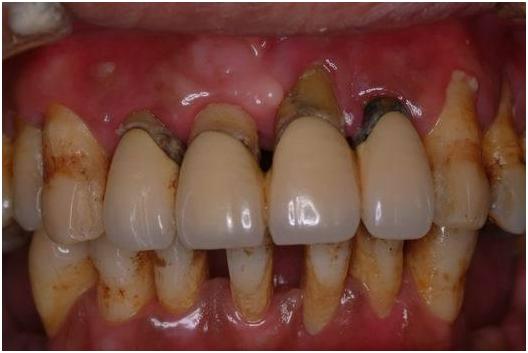

严重牙周病导致的牙齿伸长

牙周病是牙周软组织因为口腔菌斑感染引起的一种慢性炎症疾病;从龈炎开始,病菌一点点的向深层感染扩散,在侵蚀掉牙周膜和牙骨质后形成牙周病。

牙龈炎会造成牙龈萎缩,牙周病后期也会引起牙槽骨吸收,这就会使包裹在牙龈内的牙根慢慢暴露出来,患者就会感觉牙缝越来越大,甚至出现'黑三角'。

4.牙齿松动

牙槽骨吸收,牙周组织被破坏都会导致牙齿因支持力量不足而松动,当牙齿出现松动时,就说明炎症已经到深层了,这个时候一定要尽早医治,否则患牙周围其他的牙齿也容易'受牵连'导致松动脱落。